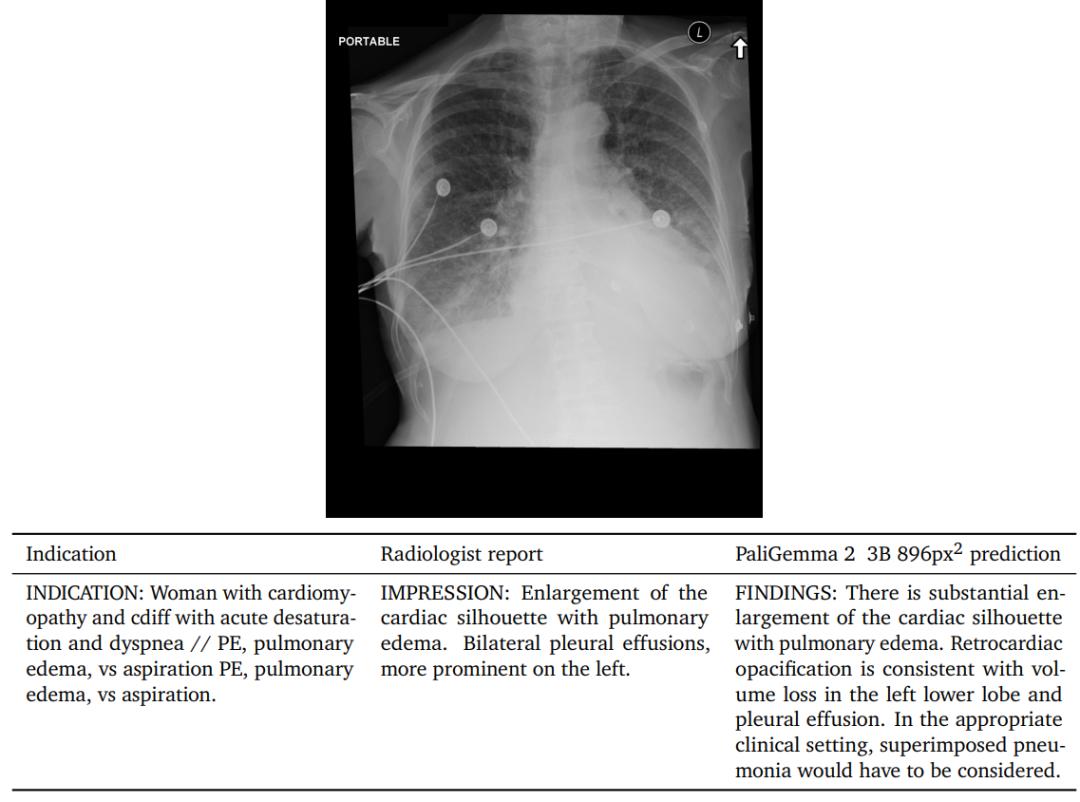

为了探索PaliGemma 2在医学领域的能力,研究人员将其用于自动胸部X光报告生成任务上,相当于对X光图像进行长描述。

MIMICCXR数据集包含37.7万张图像,及相应的放射报告;使用Gemini 1.5 pro来移除之前数据中涵盖的X光。

在使用该数据进行微调后,用RadGraph F1分数评估结果,衡量参考报告中提取的实体与生成报告之间的F1分数,可以反应报告中实体的缺失或召回情况,以及与图像特征的关系。

可以看到,PaliGemma 2模型的实现了最好的性能,提高分辨率和模型大小都能带来性能提升。